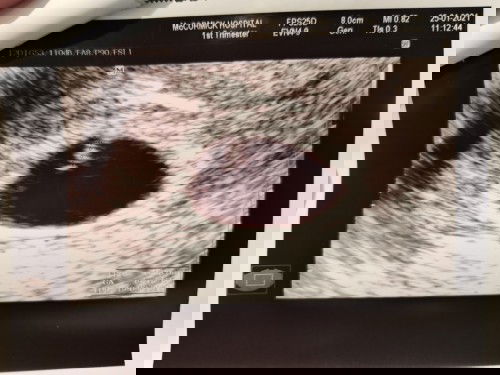

รบกวนคุณแม่ที่มีประสบการณ์ทุกท่านหน่อยค่ะ คือเราไปซาวมาครั้งแรกตอน5วีค3วัน เจอแต่ถุงตั้งครรภ์3มิล หมอเลยนัดอีกที ตอนครบ8วีค3วัน ก็คือวันนี้ พอซาวแล้ว พบว่าถุงตั้งครรภ์ใหญ่ขึ้น และเห็นจุดเล็กๆเหมือนตัวอ่อน ขนาด3มิล (ตามภาพ) เห็นหัวใจกระพริบๆช้าๆ แต่ไม่สามารถฟังเสียงได้ หมอบอกว่ายังเต้นช้าอยู่ หมอยังไม่ให้ฝากครรภ์ค่ะ นัดอีก2อาทิตย์มาใหม่ หมอไม่แนะนำหรือพูดอะไรเลย เรารู้สึกกังวลมาก ว่ามันผิดปกติอะไรหรือเปล่า มา2รอบแล้ว ยังไม่ได้ฝากครรภ์เลย ต้องมารอลุ้นอีก2อาทิตย์แหนะ เจอแบบนี้ยิ่งกังวลเลยค่ะ มีใครเจอแบบนี้บ้างไหมคะ หรือขอคำแนะนำ และขอกำลังใจหน่อยค่ะ#ขอบคุณล่วงหน้านะคะ #ท้องแรกคะ